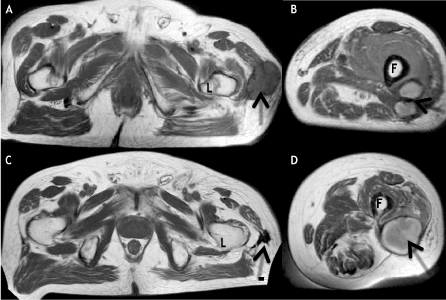

Figure 2. MRI evidence of tumor regression. 2A and 2B, Axial T1-weighted images from initial MRI reveal subcutaneous hypointense mass (arrow, 2A) posterolateral to the left femoral lesser trochanter (L), and two adjacent hyperintense masses (arrow, 2B) posterolateral to the left femoral diaphysis (F). 2C and 2D, Axial T1-weighted images from follow-up MRI demonstrate marked size/signal decrease of the mass (arrow, 2C) posterolateral to the left femoral lesser trochanter (L) as well as coalescence of the masses (arrow, 2D) posterolateral to the left femoral diaphysis (F).

Over the next 6 months there was gradual disappearance of the abdominal skin nodules and the 2 large palpable thigh masses, along with radiographic improvement of metastases in the femur and deep thigh tissues. On physical exam there were no palpable thigh masses and no abdominal wall tumors. A follow-up MRI 41 months post injury showed a) complete resolution of a large soft tissue thigh mass and fusion of 2 smaller prior masses (Figure 2). The latter mass corresponded in location to a newly palpable tender mass in the lower thigh, suspicious for recurrence. By 45 months post injury there was rapidly progressing lymphedema of all 4 limbs along with severe anemia unresponsive to steroids and the patient expired 49 months post injury.

Radiology

The initial MRI obtained 15 months post injury, at the time of pathological fracture of the femur, showed several large masses in the left thigh (Figure 2A and 2B). One of these masses underwent complete spontaneous resolution (Figure 2C). The two smaller masses were replaced by a new mass at follow-up imaging obtained 41 months post injury (Figure 2D), suspicious for possible recurrence.